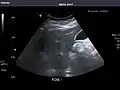

Liver: Diffusely homogeneous and normal in echogenicity. No focal mass or contour nodularity. No intrahepatic biliary ductal dilatation.

Portal Vein: Patent main portal vein.

Gallbladder: No stones, wall thickening, or pericholecystic fluid.

Common Bile Duct: Nondilated measuring 1.3 mm at the level of the porta hepatis.

Liver